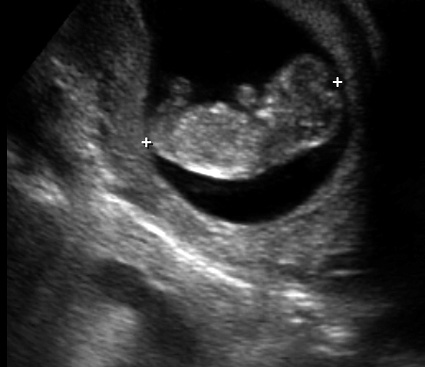

The result of one of my many appointments: the first pic of our little thumb-sucking alien baby.